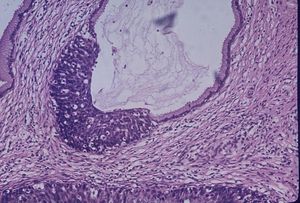

대장암 검사는 조기에 발견하면 예방이 거의 가능하다. 대장암은 대장용종이라는 양성 성장을 통해 발생하기 때문이다. 대장내시경을 통해 대장 용종을 발견하고 절제할 수 있다.[29]

대장암 검진은 충분히 일찍 실시하면 용종 단계에서 발견하여 제거할 수 있다. 암이 발생하면 결장 절제술과 같은 더 침습적인 수술이 필요하고, 암이 더 퍼지면 다른 치료 방법이 필요하다. 따라서 조기 진단은 더 침습적인 치료의 필요성을 줄여준다.[29][30]

분변 잠혈 검사법은 사망률 감소 효과가 증명되어 국가 암 검진과 선택적 암 검진 모두에서 권장된다. 대장 내시경 검사 역시 사망률 감소 효과가 증명되었지만, 무시할 수 없는 단점도 존재한다.[62]